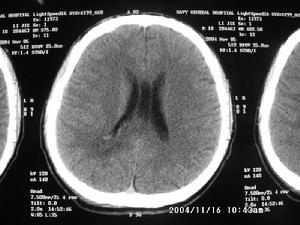

納博特囊腫超聲圖像示:

(1)本組彩色都卜勒顯示宮區宮旁血流豐富。

(2)本組液性暗區最大直徑18mm,最小直徑5mm,伴有子宮肌瘤7例(占14%),卵巢囊腫5例(占10%),盆腔積液10例(占20%),輸卵管積水2例(占4%),子宮次切術後1例(2%)。

(3)子宮頸肥大18例(占37%)。宮頸厚度在30mm以上,個別達到36mm。部分宮頸回聲可增強。

(4)頸部可見單或多個圓形或橢圓形液性暗區。單發19例(占39%),多發30例(占61%),邊界清晰,後方均伴有增強效應,其中5例還伴有囊壁鈣化。

分析:陰道超聲能彌補婦檢的不足,而且其對檢查者又具有操作簡便、診斷準確、針對性強、無創傷等優點。本組聲像圖具有一般囊腫聲像圖特徵,但其也應與子宮頸肌瘤等相鑑別。在聲像圖上子宮頸肌瘤為低回聲,CDFI示可有包膜血流,無囊腫特有的後壁增強效應。總之,陰道彩超能及時準確地查出已婚婦女的宮頸腺體囊腫,為臨床診斷及治療慢性宮頸炎提供了可靠依據宮頸腺體囊腫為宮頸慢性炎症所致,而臨床醫師僅能觀察到宮頸外口表面的小囊腫,但陰道彩超能查出宮頸深部腺體內所發生的瀦留性囊腫。納氏囊腫本身不引起患者自覺症狀,故未引起患者及臨床醫師的重視。隨著人們生活水平的提高,保健意識的增強;自從超聲診斷儀出現,體檢的婦女逐漸增多。上述49例均為體檢者,其中有宮頸炎的31例,有宮頸肥大18例,大致符合納氏囊腫的病因及病理。